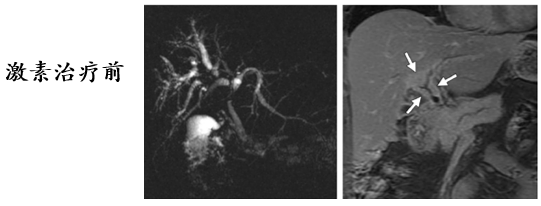

胆管受累治疗前后改变

在影像学鉴别困难时,可结合类固醇激素实验性治疗,必要时结合血清学 IgG4 水平做出分析。

糖皮质激素治疗有效,能够使受累器官和组织恢复到原来的状态